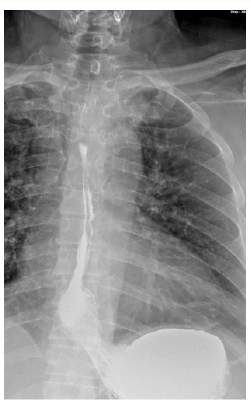

Solid Pseudopapillary Tumor of the Pancreas: A Case Report

Lamara Abdelhak, Medjahdi Sid Ahmed, Gadda Mounir, Boukhane Mohamed, Nahida Harchouche, Bloulou Mamed Lamine, Saadna Adlene and Selmani Khaled. 6(7): 12-18.